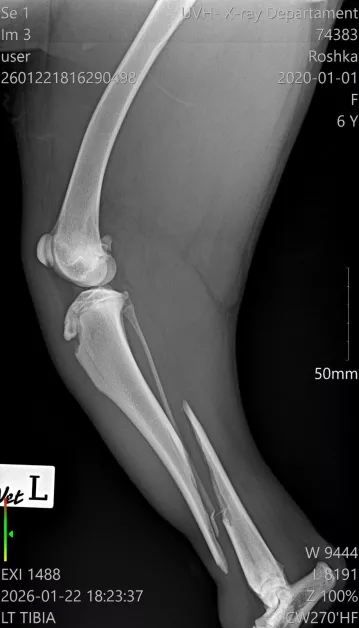

Диагнозата е тежка – две съществени фрактури на задните крака в региона на пищялите, с разбъркване и травмирани меки тъкани. По думите на ортопеда съществува действителен късмет фрактурите да бъдат закрепени с импланти и винтове, което би разрешило на Рошка още веднъж да проходи.